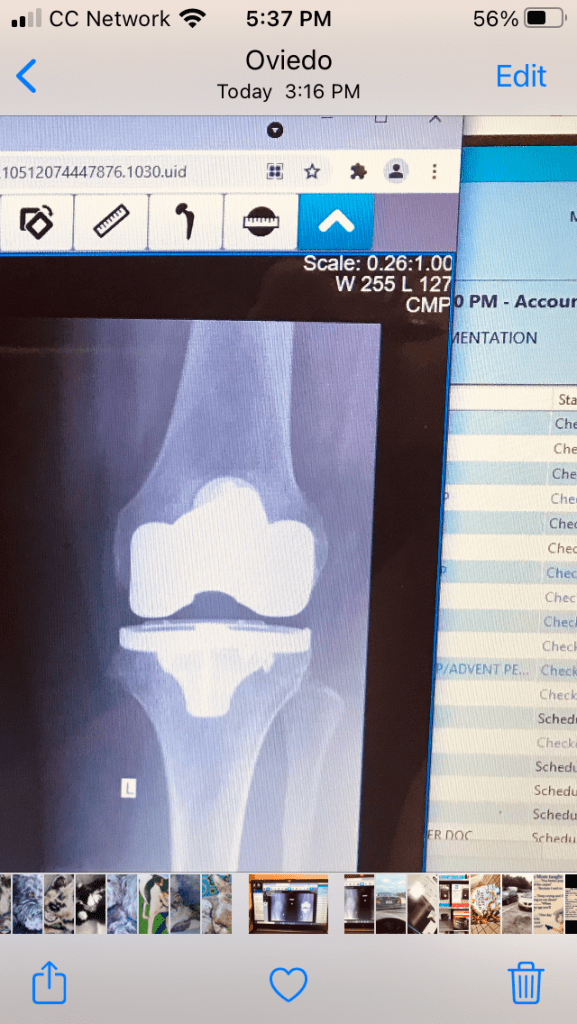

Got my left (fake) knee checked out. Yeah, I made it to my orthopedic surgeon’s after having to postpone my January appointment because all hell unleashed itself on my health: mental and physical. I knew my knee was fine.

Everything IS good there. Thank God for some happy health news. My right knee is going to have to be replaced-eventually. Right now, it’s only infrequently protesting.

When it’s due to be replaced I want Dr. H to do it cause he has a technique in which the thigh muscle doesn’t have to be cut. That mitigates a lot of pain. So, yes please, one serving of no muscle cutting.